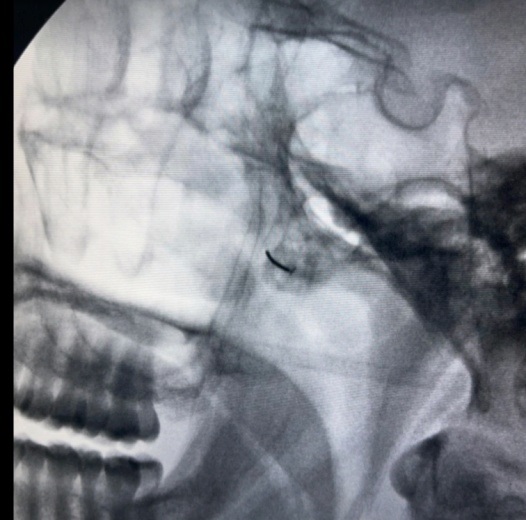

• Block του σφηνουπερώιου γαγγλίου με τοπικό αναισθητικό και κορτιζόνη

• Νευρόλυση του σφηνουπερώιου γαγγλίου με χρήση ραδιοσυχνοτήτων